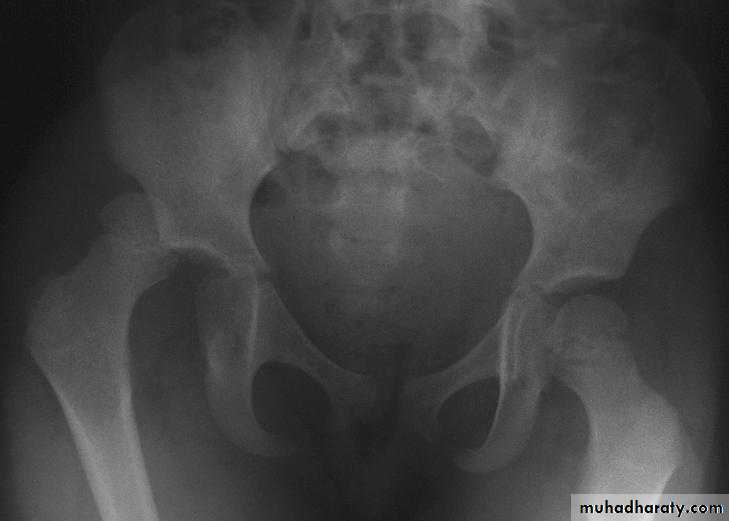

Central dislocation of the hip

fall on the side or blow over the greater trochanter may force the femoral head medially through the floor of the acetabulum .Although it is called central dislocation of the hip , it is really a fracture of the floor of the acetabulum